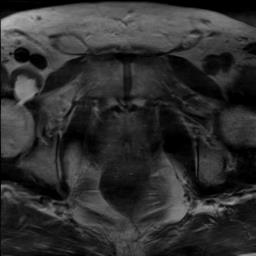

Modern deep neural networks struggle to transfer knowledge and generalize across diverse domains when deployed to real-world applications. Currently, domain generalization (DG) is introduced to learn a universal representation from multiple domains to improve the network generalization ability on unseen domains. However, previous DG methods only focus on the data-level consistency scheme without considering the synergistic regularization among different consistency schemes. In this paper, we present a novel Hierarchical Consistency framework for Domain Generalization (HCDG) by integrating Extrinsic Consistency and Intrinsic Consistency synergistically. Particularly, for the Extrinsic Consistency, we leverage the knowledge across multiple source domains to enforce data-level consistency. To better enhance such consistency, we design a novel Amplitude Gaussian-mixing strategy into Fourier-based data augmentation called DomainUp. For the Intrinsic Consistency, we perform task-level consistency for the same instance under the dual-task scenario. We evaluate the proposed HCDG framework on two medical image segmentation tasks, i.e., optic cup/disc segmentation on fundus images and prostate MRI segmentation. Extensive experimental results manifest the effectiveness and versatility of our HCDG framework.